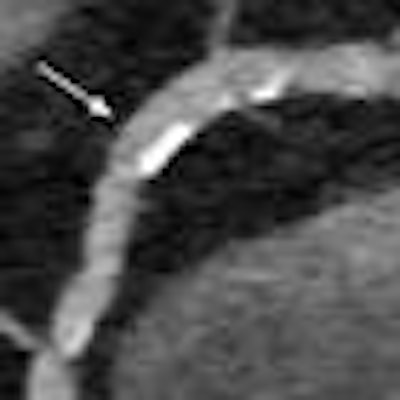

Integrated CT detector improves coronary stenosis assessment

March 10, 2013 -- VIENNA - A new integrated circuit CT detector may improve the ability of clinicians to accurately grade coronary artery stenoses visualized during coronary CT angiography, especially when combined with thin-slice imaging and iterative reconstruction, researchers reported on Sunday at ECR 2013.